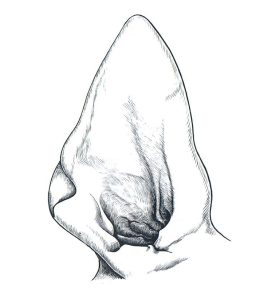

Een normaal oor bestaat uit 2 lagen huid met daartussen kraakbeen. Verder zitten er veel bloedvaten en zenuwen tussen de huid en het kraakbeen.

Wanneer zo’n bloedvat beschadigd, ontstaat een bloeding waarbij de huid van het kraakbeen gedrukt wordt. Dit zorgt voor een verdikking van de oorschelp; het karakteristieke beeld van een bloedoor. Een bloedoor ook wel othematoom genoemd zien we het meest bij de hond, maar soms ook bij de kat.

Het verschilt per hond en per keer hoe groot de verdikking is die ontstaat. Het kan enkele centimeters groot zijn, tot een verdikking waarbij de hele oorschelp een onder spanning staande bult is geworden.